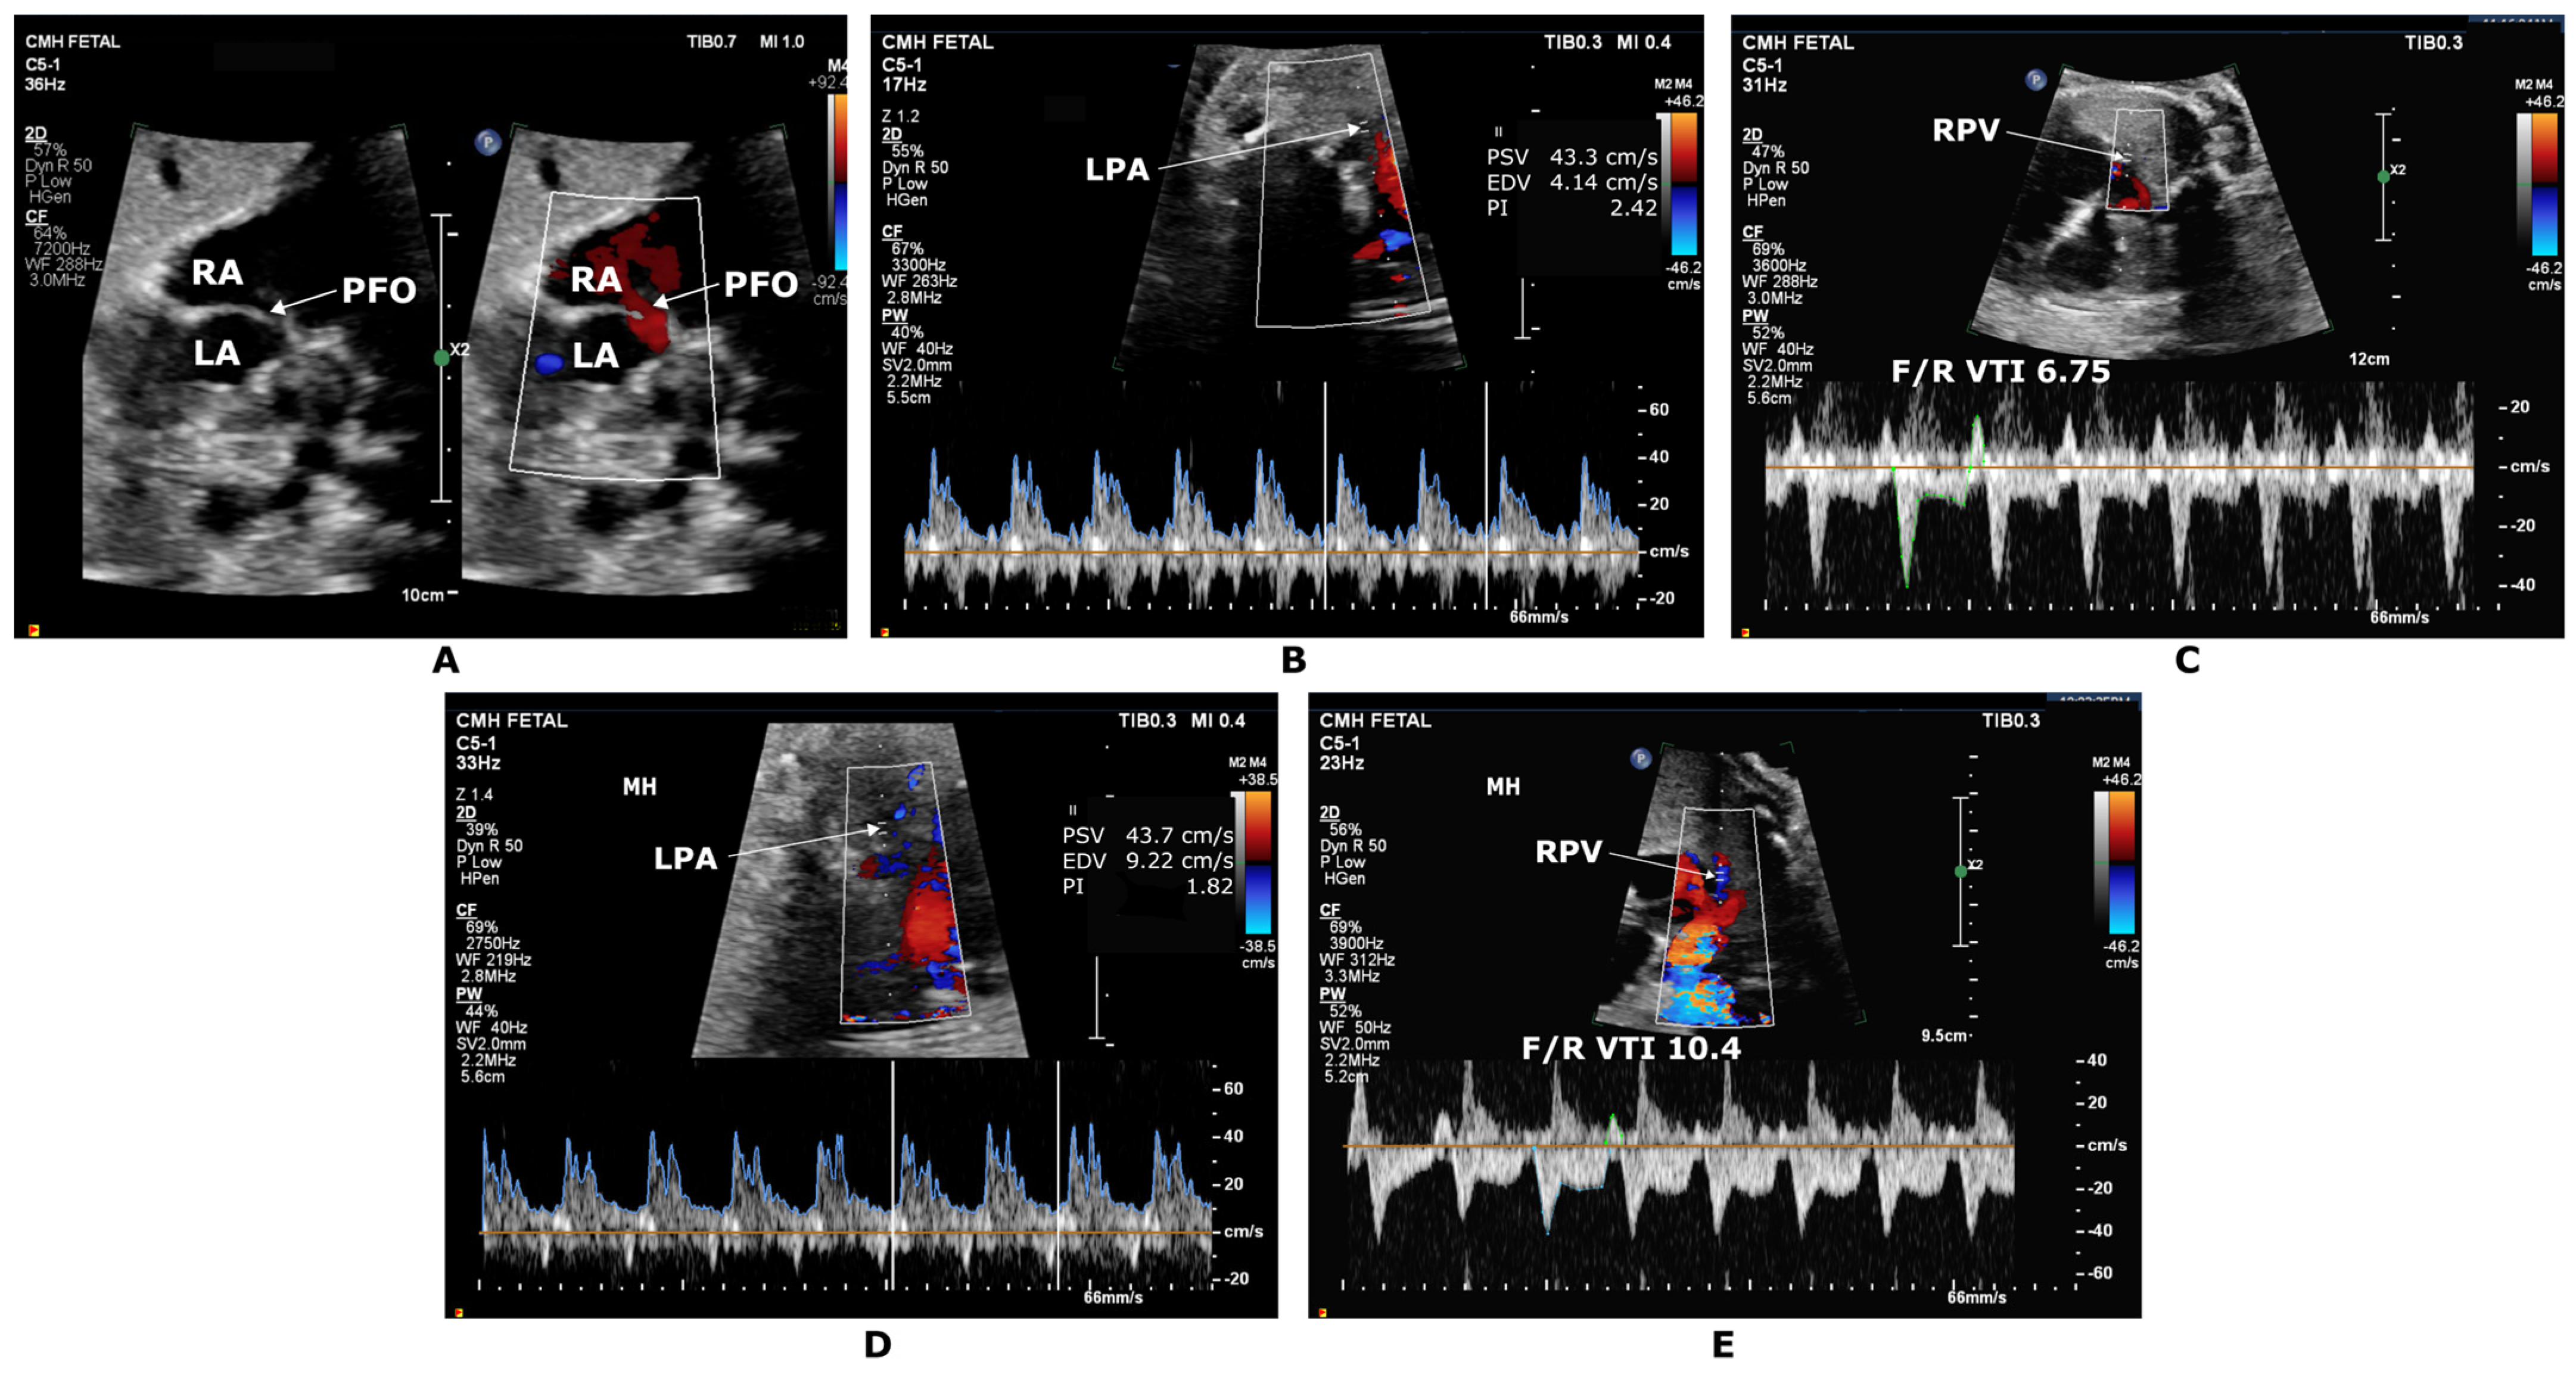

| Mardy et al. [13] 2021 | ~34 weeks GA | 27 HLHS fetuses | 100% FiO2 for 10 min via nonrebreather mask at 8 L/min effectively providing 60% inhaled FiO2 at 8L/min | Poor sensitivity with BPA PI Pulmonary Vein F/R VTI < 6.5, 100% Sensitivity and PPV in predicting emergent atrial septoplasty |